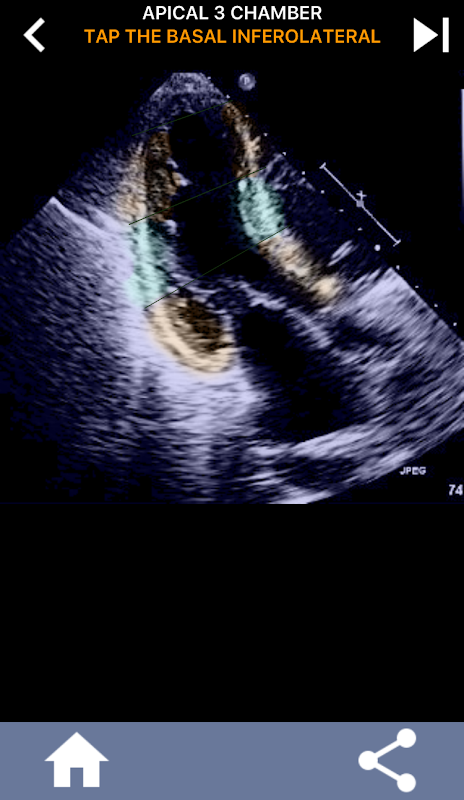

আল্ট্রাসাউন্ড ইকোকার্ডিওগ্রাফাররা আমেরিকান হার্ট অ্যাসোসিয়েশনের বাম ভেন্ট্রিকালের 17 টি সেগমেন্টে কার্ডিয়াক সেগমেন্টেশন শিখতে অপরিহার্য, যা অবস্থানের বর্ণনা দিতে চৌম্বকীয় অনুরণন ইমেজিং, কার্ডিয়াক পারমাণবিক পরীক্ষার ইত্যাদি অন্যান্য ইমেজিং পদ্ধতিগুলির দ্বারা ব্যাপকভাবে ব্যবহৃত হয়। প্রভাবিত সেগমেন্ট এবং ফাংশন। আপনার ইকোটি পড়ার সময় কতবার ব্যক্তি জিজ্ঞাসা করবে "আপনি কি দেখেছেন?" এবং প্রভাবিত এলাকা একটি সঠিক অবস্থান সঙ্গে উত্তর কি প্রত্যাশিত হয়।

এই অ্যাপ্লিকেশনটি এএএ খণ্ডিত মায়োকার্ডিয়াম দেখানো সমস্ত ইকো ভিউ ধারণ করে এবং আপনি সঠিক সেগমেন্টটি ট্যাপ করতে কুইজ করবে। আমি ব্যক্তিগতভাবে যে শিখতে দ্রুত / শিখতে বিষয় যখন আমার পুনরাবৃত্তিমূলক quizzing আমার জন্য ভাল কাজ করে। যদি আপনি আল্ট্রা / টিটিই অধ্যয়নরত আল্ট্রাসাউন্ড শিক্ষার্থী হন তবে আমি মনে করি এটি আপনার গবেষণার জন্য একটি চমৎকার পরিপূরক হবে।